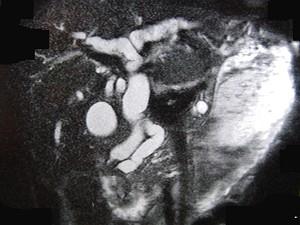

问题 患者男,47岁,进行性黄疸,发热,腹胀,影像检查如图,最可能的诊断是 ( )

选项 A、十二指肠壶腹癌 B、胰头癌 C、胆总管结石 D、胆总管癌 E、胆总管囊肿

答案 A